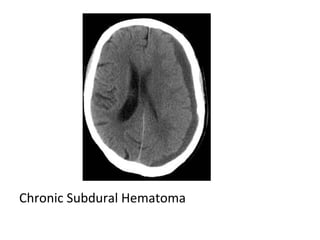

7-Hematoma :

-Subacute to chronic